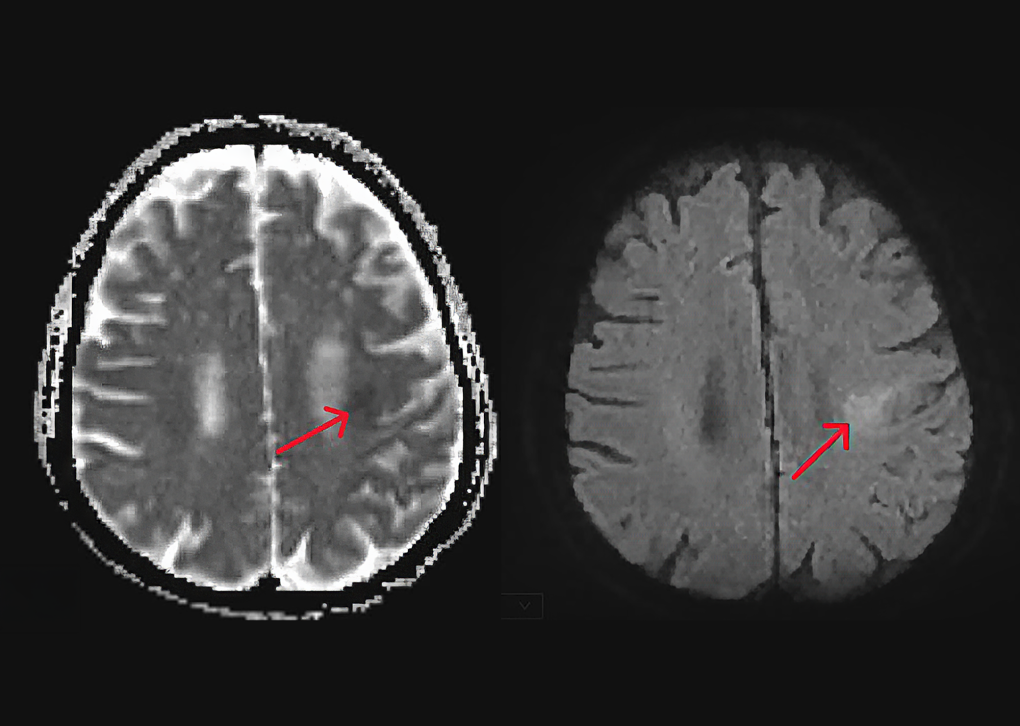

Người bệnh được chụp MRI 3 Tesla sọ não thay vì chụp CT theo quy trình cấp cứu đột quỵ thông thường. Chụp MRI giúp bệnh nhân cao tuổi có bệnh nền suy thận nặng tránh được tác dụng phụ của thuốc cản quang. Đồng thời, kỹ thuật này hỗ trợ đánh giá chính xác thêm các ổ vi xuất huyết (các nốt chảy máu nhỏ) trong não.

Vị trí nhồi máu não vùng thái dương trái của cụ Khái trên hình chụp MRI 3 Tesla. Ảnh: Bệnh viện Đa khoa Tâm Anh

Kết quả chụp MRI 3 Tesla cho thấy cụ Khái nhồi máu não vùng thái dương bán cầu não trái, không xảy ra tắc động mạch lớn trong não. Bác sĩ chỉ định truyền thuốc tiêu sợi huyết (rTPA) qua đường tĩnh mạch. Liều dùng và tốc độ truyền thuốc được cân chỉnh phù hợp với tình trạng đột quỵ, bệnh nền đồng mắc và tuổi cao của người bệnh.